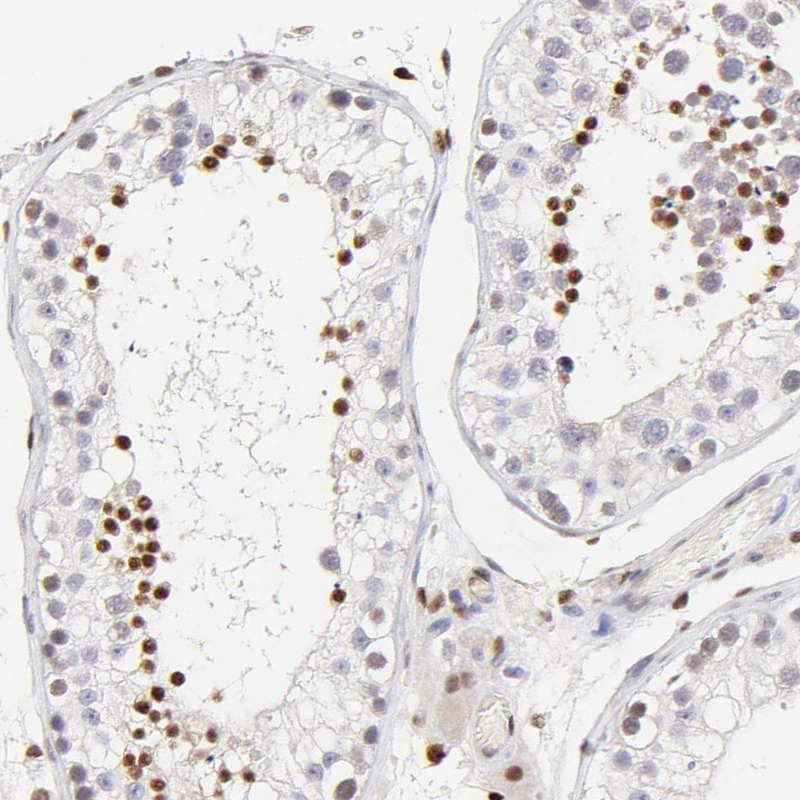

Immunohistochemistry analysis in human skin and pancreas tissues using HPA002926 antibody. Corresponding KLF4 RNA-seq data are presented for the same tissues.